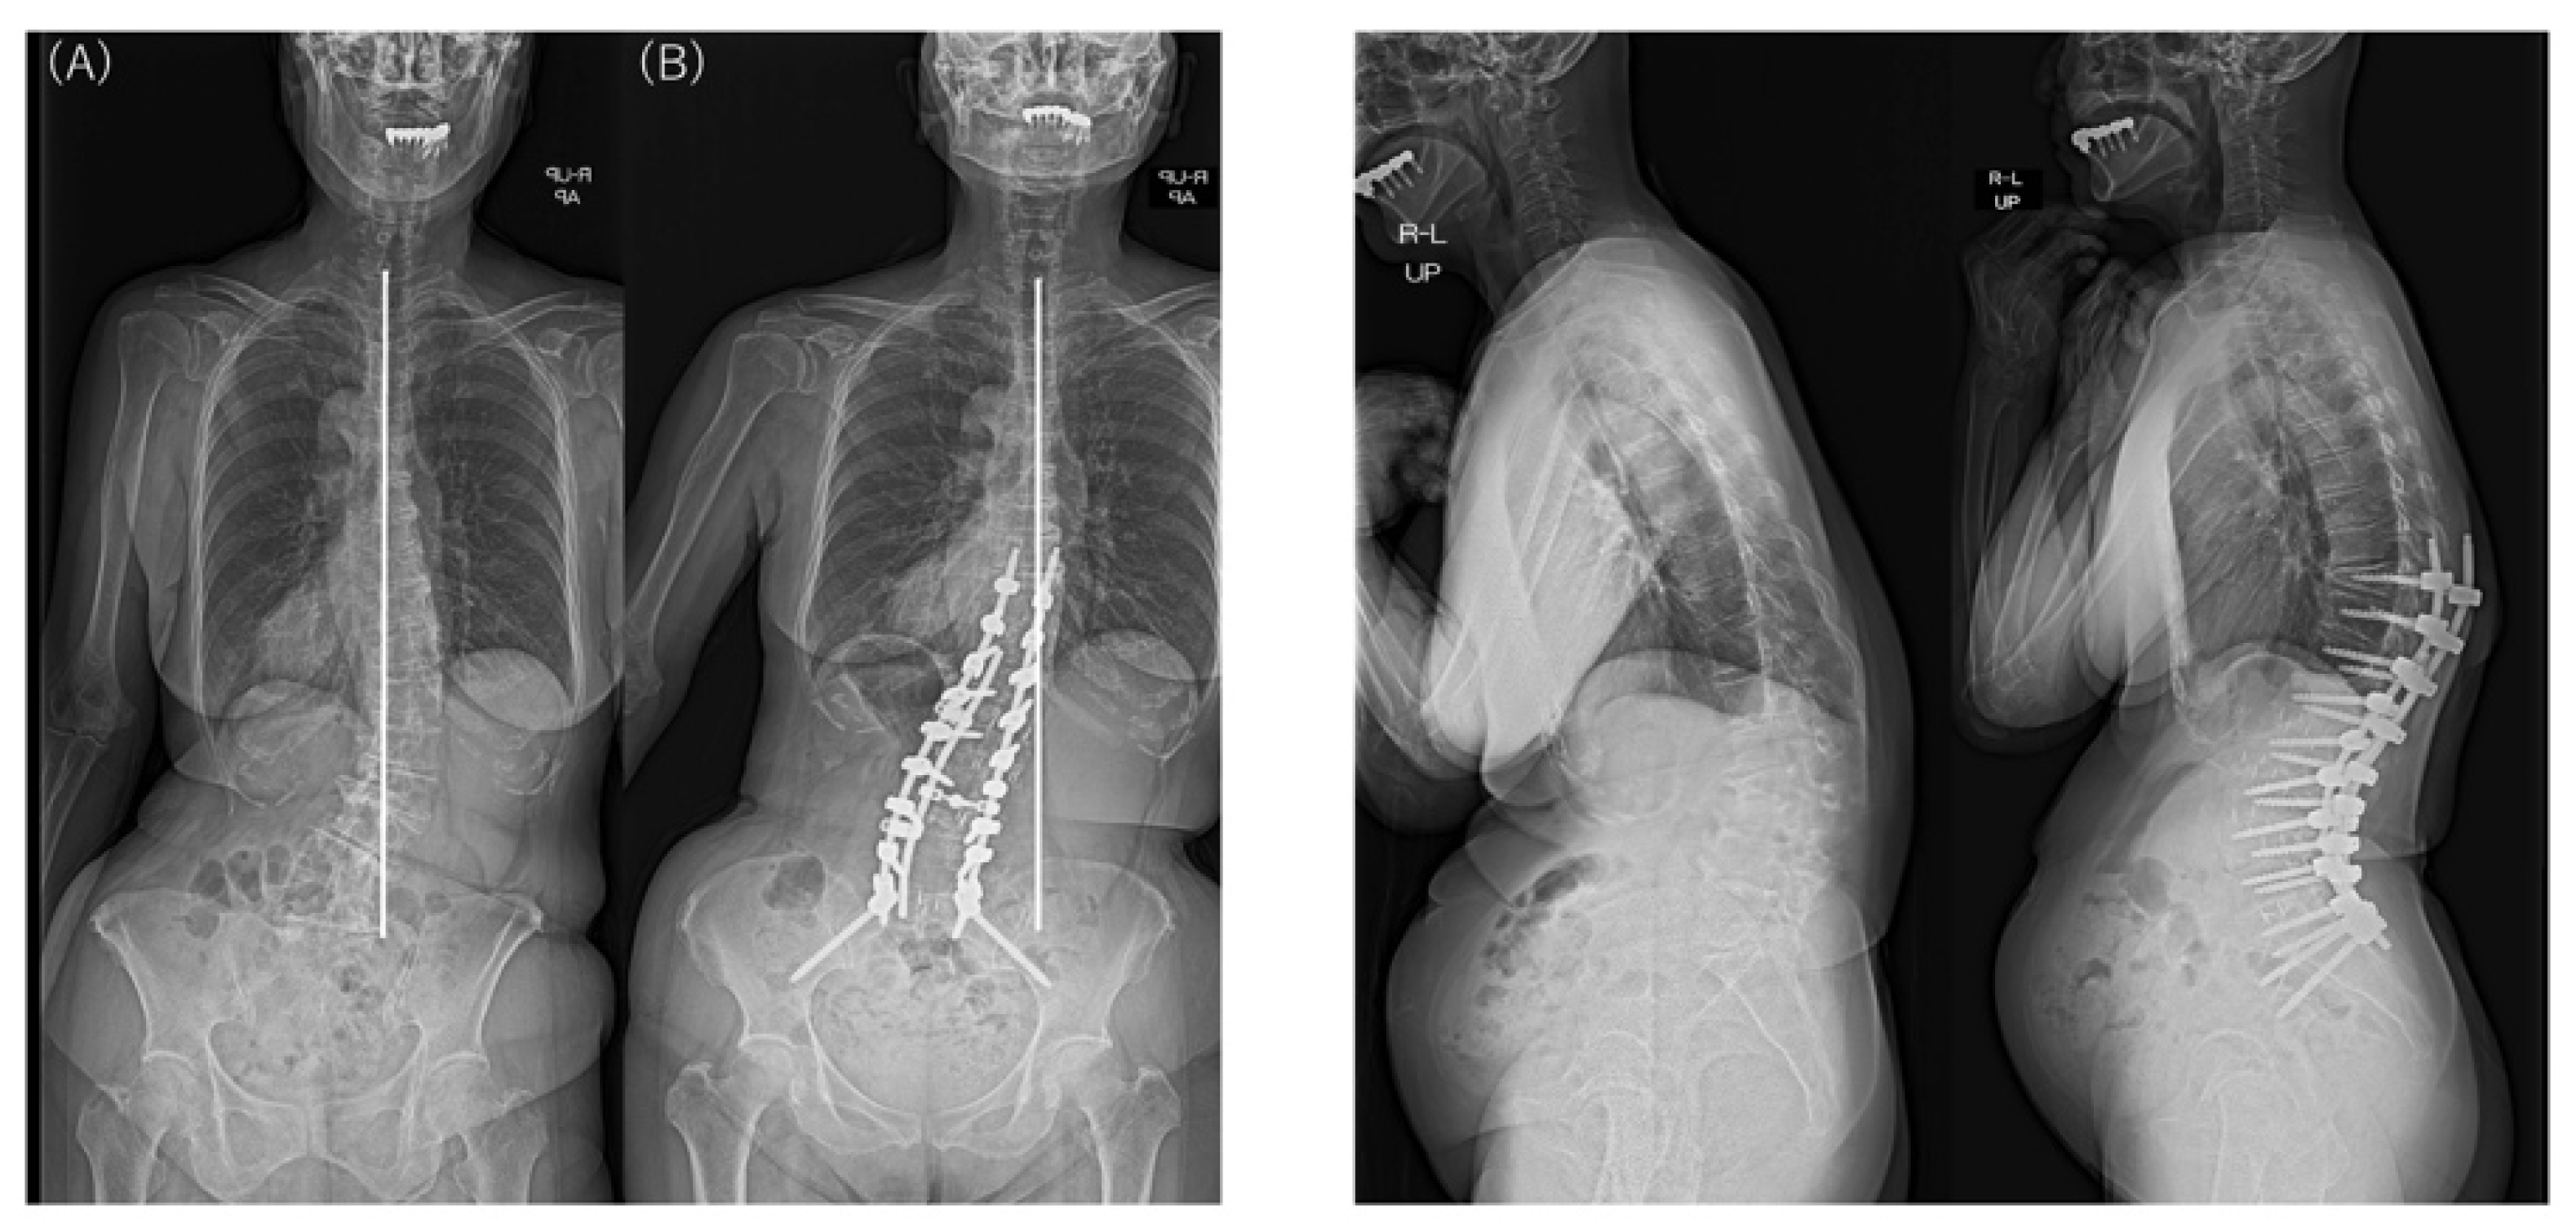

| Major Cobb angle (°) | Preop | 50.0 (11.4) | 44.3 (11.4) | 48.8 (11.5) | 0.286 |

| Last | 12.9 (11.9) | 14.2 (8.0) | 13.2 (11.1) | 0.810 | |

| p † | <0.001 * | 0.002 * | <0.001 * | ||

| │CBD│ (mm) | Preop | 78.4 (51.6) | 46.9 (21.7) | 71.9 (48.5) | 0.159 |

| Last | 22.8 (28.0) | 38.5 (20.4) | 26.0 (27.0) | 0.211 | |

| p † | <0.001 * | 0.506 | <0.001 * | ||

| Coronal L4 tilt (°) | Preop | 16.0 (6.8) | 28.7 (10.3) | 18.6 (9.1) | 0.001 * |

| Last | 7.3 (3.4) | 14.0 (5.1) | 8.7 (4.6) | 0.001 * | |

| p † | 0.002 * | 0.008 * | <0.001 * | ||

| Type 1A | 23 | 16 | 7 | 69.6% |

| Type 2A | 6 | 1 | 5 | 16.7% |